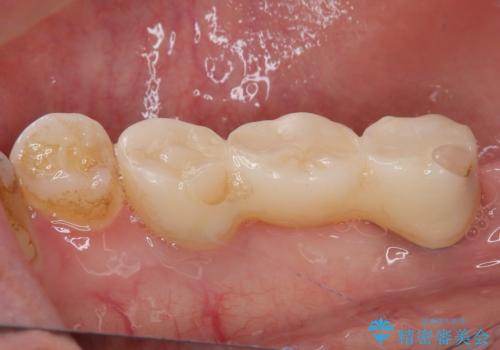

- ブリッジが装着されている奥歯がぐらぐらするとのことで来院された患者様です。

診察を行ったところ、手前の歯は歯根が破折しており、抜歯が必要な状態でした。

左右ともに臼歯部しか咬んでおらず、ブリッジの手前側の歯が破折したことで大きく揺さぶられてしまい、奥側の歯も周辺の歯が著しく吸収し、抜歯が必要な状態でした。

ブリッジの支台歯2本を抜歯し、反対側の咬合負担を軽減するために、通常よりも短い待機時間で2本のインプラントを埋入することとしました。